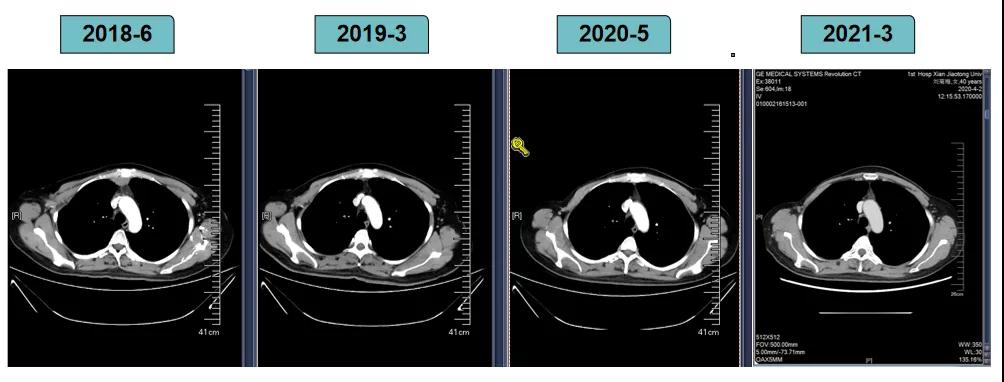

影像学评估-纵膈淋巴结:

影像学评估-肝脏: